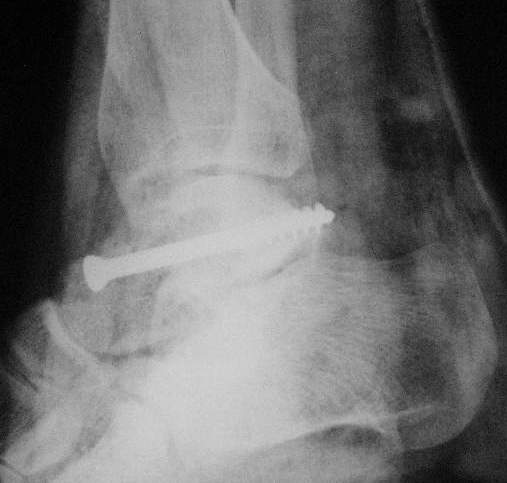

Второй случай прооперирован вчера.

10 дней назад поступил с открытым повреждением медиальной лодыжки и переломо вывихом таранной кости. Ургентно сделана репозиция с наложением наружного фиксатора + Irrigation&Debridment.

Во время репозиции выявили повреждение заднего сухожилия м. тибиалис и задней большеберцовой артерии. Медиальную рану удалось закрыть частично и установлен вакуум.

Дважды провели Irrigation&Debridment с заменой вакуума.

Вчера провели фиксацию.

Из-за многооскольчатости дистальной части малоберцовой, где невозможно было провести фиксацию шурупами, перелом зафиксирован подпирающей пластиной, которая должна служить дополнением отсутствующей дистальной части малоберцовой (lateral cortex substitute).

Для стабильности два шурупа на синдесмоз.

Медиальную рану с приближенными краями продолжаем вакуумировать (KCI). Наружный фиксатор оставлен на пару недель, надеюсь, небольшая рана будет гранулировать и закроется без кожной пластики. Фиксация медиальной ложыжки не планируется.